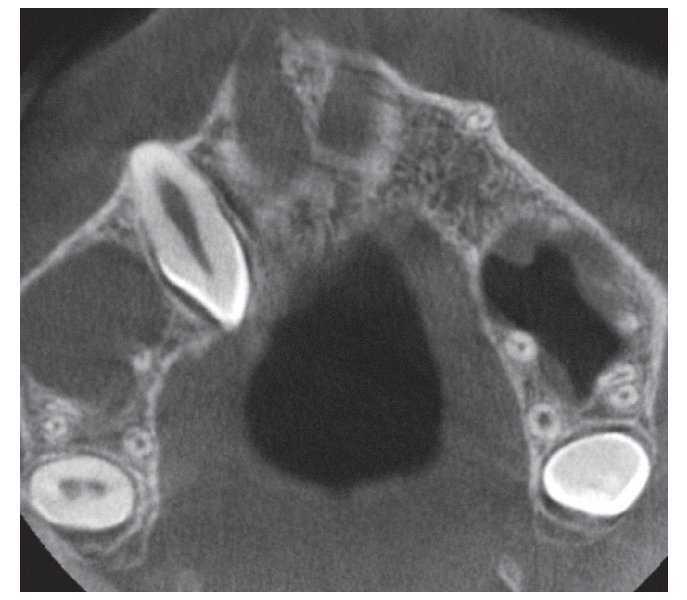

Se obtuvo una tomografía volumétrica digital dental para evaluar una posible movilización del diente 13. En la reconstrucción panorámica (fig. 1) se visualiza el diente 13 muy desplazado en sentido craneal, situándose inmediatamente debajo y cerca de la línea media del seno maxilar derecho. En el plano axial (fig. 2) se observa que la parte coronal del diente ha sufrido una malrotación hacia distal. La reconstrucción sagital (fig. 3) muestra un fragmento apical de la raíz del diente 13 muy curvado hacia craneal.

Figura 2. Tomografía volumétrica digital dental: plano axial.